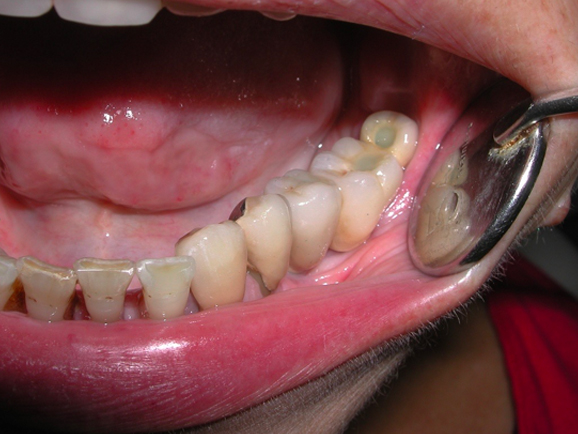

GLI ESITI

Rigenerazione ossea del pavimento del seno mascellare con incremento verticale di 12 mm ed orizzontale di 10 mm

Risultati estetici e funzionali conseguiti con la CHIRURGIA RIGENERATIVA